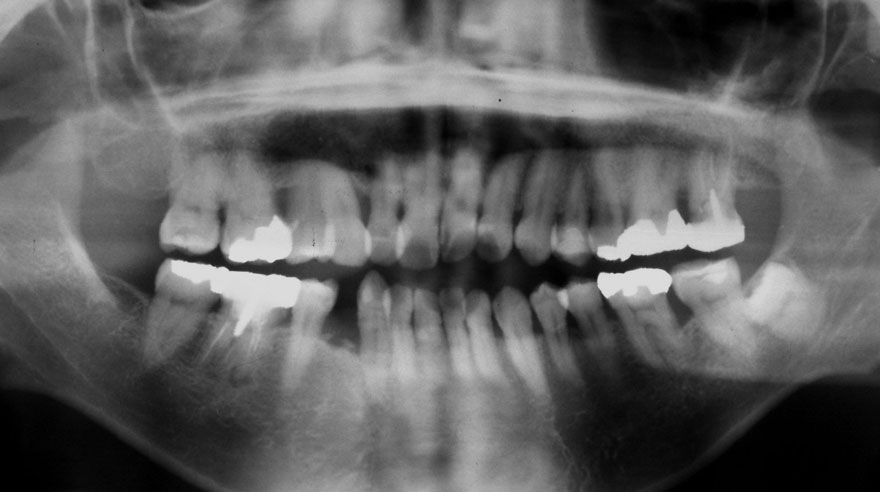

初診時 25歳 女性 平均歯槽骨喪失量:1.11mm

河田歯科医院

22年後 47歳

平均歯槽骨喪失量:1.31mm

22年間喪失量:-0.19mm

年間喪失速度:-0.009mm

(ケア頻度:2.35ヵ月ごと)